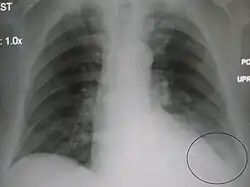

AP CXR showing left lower lobe pneumonia associated with a small left sided pleural effusion -

AP CXR showing right lower lobe pneumonia -